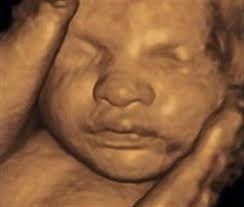

Keajaiban penciptaan manusia terungkap melalui tahap-tahap perkembangan janin yang digambarkan oleh Al-Quran. Ia dimulai dengan pembentukan sel-sel germinal pada orang tuanya. Ketika sperma bertemu dengan ovum, maka keduanya membentuk zigot (nutfah amsyaj) yang kemudian menjadi gumpalan seperti lintah (‘alaqah) kemudian menjadi segumpal daging sekunyahan (mudghah), lalu berubah menjadi tulang yang tertutup dengan daging. Dalam jangka waktu yang telah ditentukan, sel-sel tumbuh menjadi makhluk lain yang dinamis dan bergerak dalam rahim ibunya, dengan ekspresi wajah terlihat jelas. Setelah revolusi teknologi terjadi akhir-akhir ini hingga diciptakan sebuah alat scan embrio, maka kita sekarang dapat melihat embrio tersenyum dan menangis dalam perut ibu sebelum mereka melihat cahaya di bumi.

Ada beberapa model pemindaian medis dan kebidanan pada USG. Standar diagnostik umum kebidanan adalah pemindaian model 2D. Dalam pemindaian janin 3D bukan gelombang suara yang dikirim langsung ke bawah dan dipantulkan kembali, tetapi dikirim pada sudut yang berbeda. Gema yang kembali diproses oleh program komputer yang canggih sehingga menghasilkan volume gambar tiga dimensi dari permukaan janin atau organ internal, cara yang sama yang digunakan alat CT scan untuk membangun sebuah gambar dari beberapa x-ray. 3D ultrasound memungkinkan kita untuk melihat lebar, tinggi dan kedalaman gambar dalam banyak cara yang sama seperti film 3D tapi tidak ada gerakan ditampilkan. Sedangkan model 4D ultrasound menambahan gerakan dengan merangkai 3D ultrasound secara berturut-turut.

Teknik pemindaian termodern telah menghasilkan gambar yang menakjubkan dari dalam rahim yang menunjukkan bahwa bayi rupanya tersenyum dan menangis. Hingga kini, para dokter tidak berpikir bahwa bayi tidak berekspresi sampai setelah kelahiran. Mereka meyakini bahwa bayi belajar untuk tersenyum dengan meniru ibunya. Bayi biasanya tidak tersenyum setelah lahir sampai mereka berusia sekitar enam minggu.

Ilmuwan bukan satu-satunya yang terkejut oleh gambar ini, tetapi orang-orang biasa lebih terkejut. Foto-foto ini benar-benar membangkitkan dalam jiwa manusia rasa kagum yang luas biasa terhadap ciptaan Allah. Gambar-gambar tersebut dapat memicu emosi belas kasih orang tua dan gembira ketika melihat janin tersenyum, dan emosi belas kasih ketika anda melihat janin menangis.

Pada emosi ini, sebuah pertanyaan penting harus diajukan: jika janin masih dalam rahim ibunya dan ia tidak melihat cahaya lagi, tidak melihat ibunya menangis atau tersenyum, lalu siapa yang mengajarkan janin ini menangis dan tersenyum? Pertanyaan ini bahkan dilontarkan oleh para ilmuwan. Profesor Stuart Campbell mengatakan, “Ada apa di balik senyum itu? Tentu saja, saya tidak bisa menjawabnya. Tapi, muncul sudut dan tonjolan pipi … aku pikir itu pasti ada indikasi kepuasan dalam sebuah lingkungan yang bebas stres. “